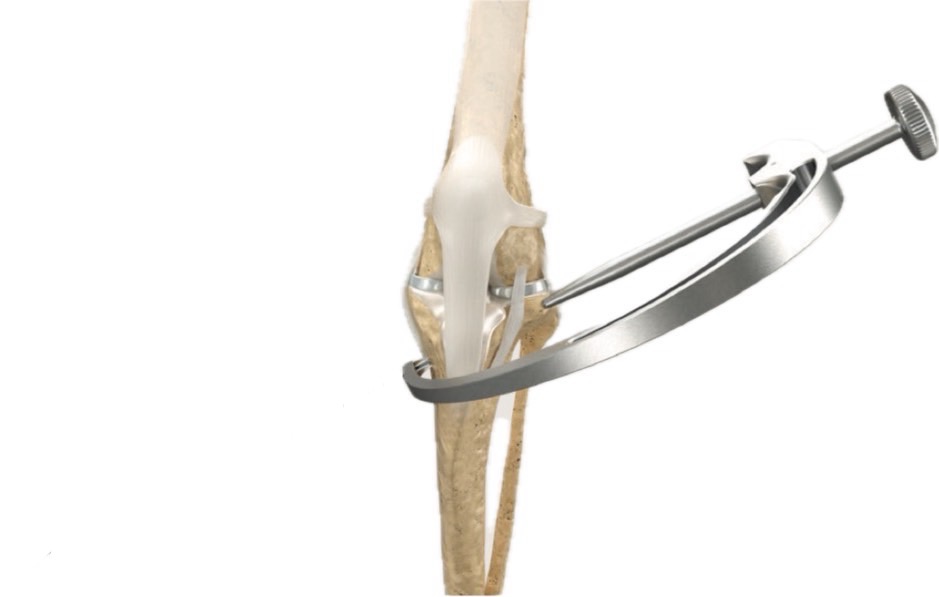

楕円と円の構造の膝関節の中から、等尺点は既に見つかっていました。F2-T3siteと呼ばれる、大腿骨の特定部位(F2)と脛骨の特定部位(T3)の2点を結んだ線は、膝を曲げ伸ばししてもほとんど距離が変わらないことがわかっています。残る課題は、その2点へのアプローチ法と、十分な強度を持つ人工繊維、F2-T3siteに正確に人工繊維を設置する方法でした。これらの課題をクリアできたら、繊維の強度不足による破綻や、たわみから生じる不安定性の残存などの、従来のECRの問題点が理論的には解消されます。

オルソスタは、現時点で、獣医学で使用できる人工繊維としては最強クラスと言えます。また、特殊な道具を用いて、等尺点F2-T3siteに正確なアプローチも可能になりました。TPLOが人工物の強度に頼らない術式という点でやはり抜きん出た存在ではあるものの、特定の条件下では、オルソスタも十分に検討に値する選択肢となっていると当院では結論づけています。